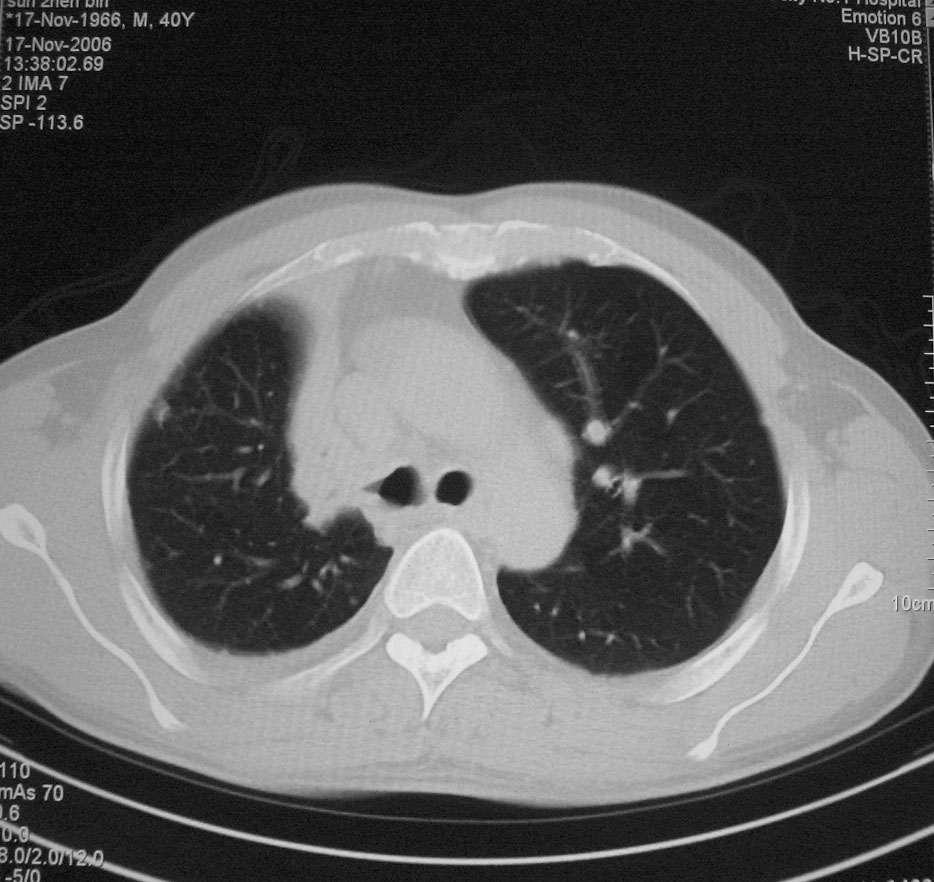

标题: CT5485:[原创]肺部占位请讨论

右上叶支气管肺癌并右上叶阻塞性不张,右侧少量胸腔积液.

右上肺中央性肺癌伴右侧胸腔少量积液!右上肺胸膜下还有一小病灶,不完全排除结核,但个人支持恶性肿瘤!建议早穿刺活检。

右肺上叶中央型肺癌并上叶肺不张、纵隔淋巴结肿大.右侧少量胸腔积液。

右上肺中心型肺癌并肺不张,纵膈淋巴结肿大。右侧少量胸腔积液。

右肺上叶不张,考虑中央型肺癌。右侧胸膜肥厚